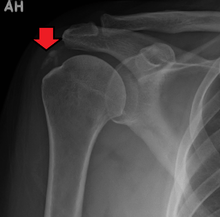

A plain X ray of the shoulder showing calcific tendinitis | |

Calcific tendinitis is a form of tendinitis, a disorder characterized by deposits of hydroxyapatite (a crystalline calcium phosphate) in any tendon of the body, but most commonly in the tendons of the rotator cuff (shoulder), causing pain and inflammation. The condition is related to and may cause adhesive capsulitis ("frozen shoulder").

The calcific deposits are visible on X-ray as discrete lumps or cloudy areas. The deposits look cloudy on X-ray if they are in the process of reabsorption, and this is also when they cause the most pain. The deposits are crystalline when in their resting phase and like toothpaste in the reabsorptive phase. However, poor correlation exists between the appearance of a calcific deposit on plain X-rays and its consistency on needling. Ultrasound is also useful to depict calcific deposits and closely correlates with the stage of disease.[1]